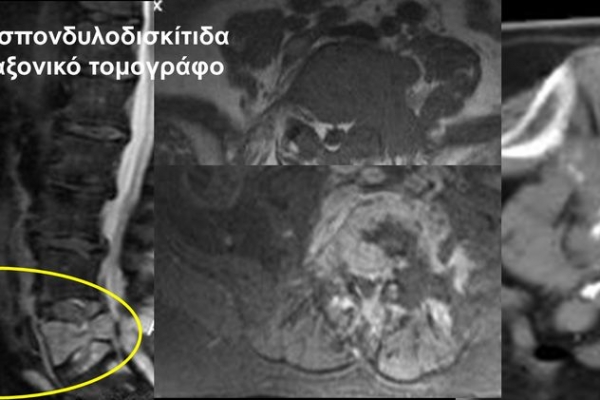

Η οστική βιοψία και η βιοψία όγκων μαλακών μορίων χρησιμοποιείται για την ιστολογική διάγνωση αλλοιώσεων (καλοήθων - κακοήθων / πρωτοπαθών ή μεταστατικών) ή για τη λήψη υλικού προς καλλιέργεια ώστε να αναδειχθεί το μικρόβιο που προκαλεί τη λοίμωξη του μυοσκελετικού συστηματος (πχ σπονδυλοδισκίτιδα). Η βιοψία υπό συνεχή απεικονιστική καθοδήγηση συμβάλλει στην υψηλή ακρίβεια τοποθέτησης της βελόνης εντός της βλάβης με ασφαλή προσπέλαση. Η χρήση σύγχρονων ομοαξονικών συστημάτων βιοψίας (coaxialtechnique) επιτρέπει την λήψη πολλαπλών δειγμάτων με μια μόνο παρακέντηση.